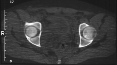

Radiographs:

Radiographs revealed a vertical buckle fracture of the right inferior sacrum, oblique fractures of the superior and inferior rami on the right and a fracture through the medial acetabulum. Obturator and iliac oblique inlet and outlet pelvic views, and a thin cut CT with 3-D reconstruction of the acetabulum were performed. These elucidated a comminuted anterior wall with fracture line extending to the posterior column. The posterior column was non-displaced. The pelvic fracture was non-displaced.

1. Right T-shaped acetabular fracture with anterior wall comminution.